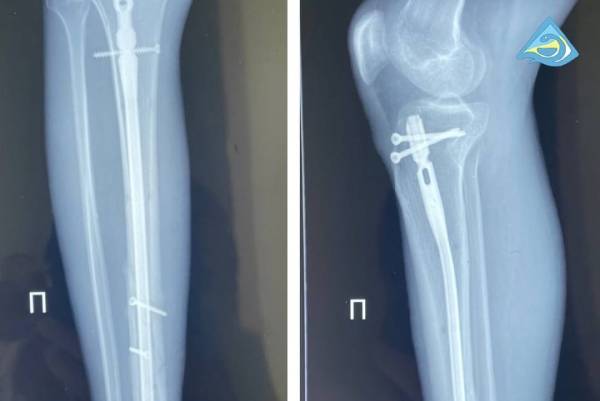

У него была сочетанная травма, политравма: множественные закрытые переломы костей таза, рёбер, обеих голеней и стоп.

Всего в республиканской больнице мужчине выполнили четыре операции. В самой обширной из них было задействовано одновременно четыре травматолога, два анестезиолога. Специалистам необходимо было анатомически точно сопоставить фрагменты повреждённых костей, а затем зафиксировать специальными имплантами.